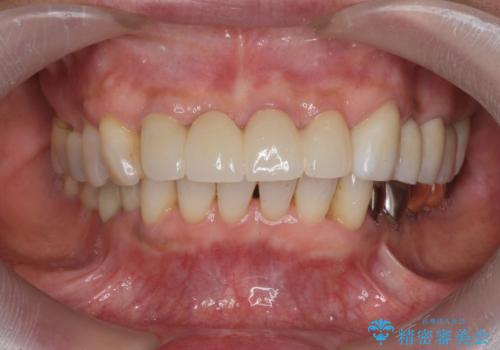

3. ぐらつく前歯 ブリッジ治療の治療後